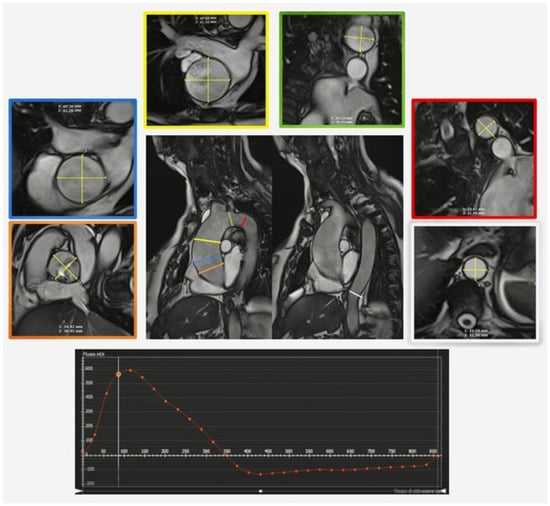

1.2. Magnetic Resonance

- Messroghli, D.R.; Moon, J.C.; Ferreira, V.M.; Grosse-Wortmann, L.; He, T.; Kellman, P.; Mascherbauer, J.; Nezafat, R.; Salerno, M.; Schelbert, E.B.; et al. Clinical recommendations for cardiovascular magnetic resonance mapping of T1, T2, T2* and extracellular volume: A consensus statement by the Society for Cardiovascular Magnetic Resonance (SCMR) endorsed by the European Association for Cardiovascular Imaging (EACVI). J. Cardiovasc. Magn. Reson. 2017, 19, 75. [Google Scholar] [CrossRef]

- Meloni, A.; Gargani, L.; Bruni, C.; Cavallaro, C.; Gobbo, M.; D’Agostino, A.; D’Angelo, G.; Martini, N.; Grigioni, F.; Sinagra, G.; et al. Additional value of T1 and T2 mapping techniques for early detection of myocardial involvement in scleroderma. Int. J. Cardiol. 2023, 376, 139–146. [Google Scholar] [CrossRef]

- Meloni, A.; Pistoia, L.; Positano, V.; Martini, N.; Borrello, R.L.; Sbragi, S.; Spasiano, A.; Casini, T.; Bitti, P.P.; Putti, M.C.; et al. Myocardial tissue characterization by segmental T2 mapping in thalassaemia major: Detecting inflammation beyond iron. Eur. Heart J.-Cardiovasc. Imaging 2023. [Google Scholar] [CrossRef]

- Meloni, A.; Martini, N.; Positano, V.; D’Angelo, G.; Barison, A.; Todiere, G.; Grigoratos, C.; Barra, V.; Pistoia, L.; Gargani, L.; et al. Myocardial T1 Values at 1.5 T: Normal Values for General Electric Scanners and Sex-Related Differences. J. Magn. Reson. Imaging 2021, 54, 1486–1500. [Google Scholar] [CrossRef]

- Meloni, A.; Nicola, M.; Positano, V.; D’Angelo, G.; Barison, A.; Todiere, G.; Grigoratos, C.; Keilberg, P.; Pistoia, L.; Gargani, L.; et al. Myocardial T2 values at 1.5 T by a segmental approach with healthy aging and gender. Eur. Radiol. 2022, 32, 2962–2975. [Google Scholar] [CrossRef]